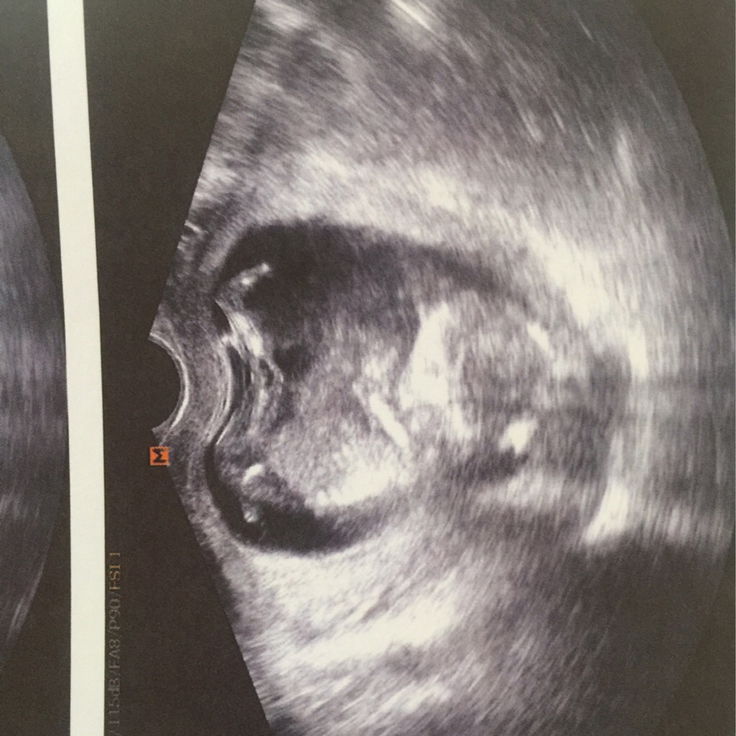

วันนี้เวลา8.30น. กำลังลุกอาบน้ำแต่งตัวไปทำงานแต่มีเลือดไหลเต็มเลยคะ ตอนนั้นกังวลมากทำอะไรไม่ถูกเลยคิดว่าจะเสียลูกไปส่ะแล้ว(ตอนนั้นคือใจสลายร้องไห้ไม่หยุดเลยคะ) คือตอนรู้ว่าท้องไปฝากครรภ์ที่คลินิกและหมอตรวจไม่ละเอียดไม่รู้เลยว่าตัวเองรกเกาะต่ำ จนวันนี้พอมีเลือดออกเราไม่ลีรอเลยคะไป รพ.เอกชน เพราะคิดว่าอยากตรวจไวที่สุดเผื่อจะมีโอกาสช่วยลูก และก็มีโอกาสจริงๆคะหมอตรวจภายในและซาวด์ดู ตอนนี้14weekแล้วคะหัวใจเต้นดีและฉีดยากันแท้งและนอนพัก7วันคะ เกือบเสียลูกไปเพราะวางใจมากเกินไป เหตุการณ์ครั้งนี้ทำให้เราระวังตัวเองมากขึ้นไปอีก ฝากถึงแม่ๆที่กำลังตั้งครรภ์นะคะหากมีเลือดออกหรืออะไรผิดปกติไปพบแพทย์ทันทีเพื่อลูกของเราคะ ตอนนี้สบายใจขึ้นมากแล้วคะ เหลือแต่ระวังตัวและดูแลตัวเองให้มากๆ(ตอนท้องแรกๆหนูทำงานปกตินะคะ) ตอนนี้คงต้องพักยาวๆ เป็นกำลังใจให้แม่ๆทุกๆคนนะคะ✌?☺️? #คุณหมอแซวมาว่าน่าจะเป็นผู้ชายรอลุ้นอีกทีตอน5mคะ ว่าได้เพศอะไร❤️??